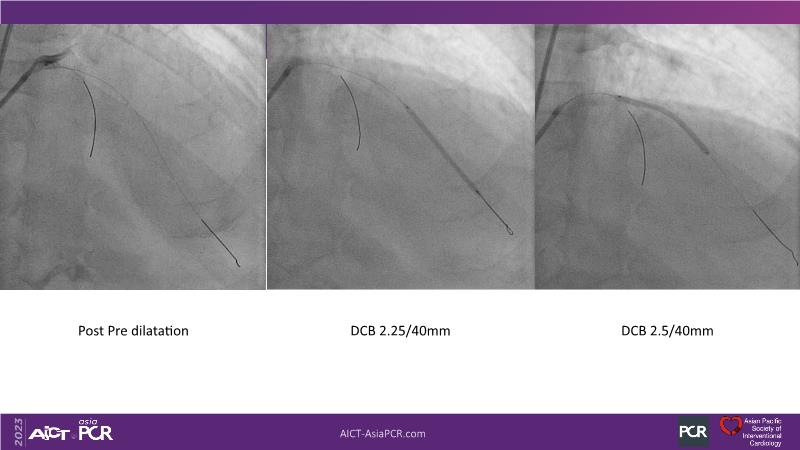

Leave nothing behind: DCB-only PCI strategy - How DCB evidence has changed today's practice?

This session offers an opportunity to stay informed about the recent developments in the International DCB Consensus Group, gain insights into the latest clinical data and real-world experiences related to drug-coated balloon (DCB)-only PCI, understand the safety aspects of DCB in managing complex PCI cases, and participate in an interactive discussion with experts.